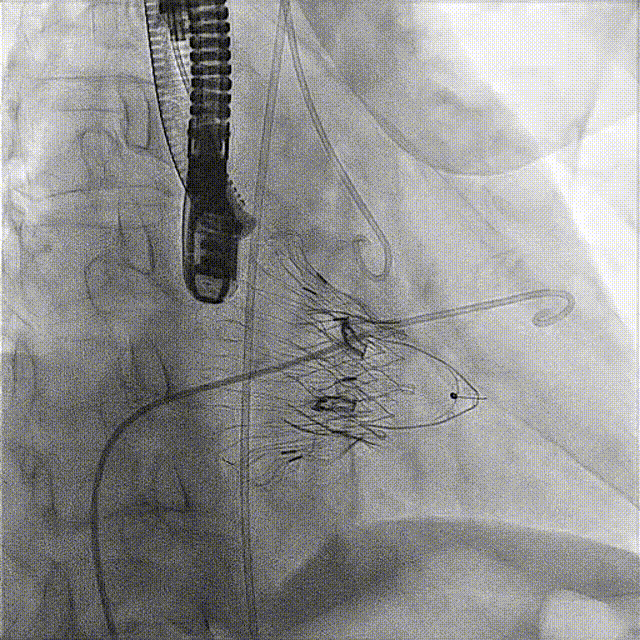

術(shù)后DSA

術(shù)前經(jīng)過全面系統(tǒng)的評估后,考慮患者存在高齡、心功能減低、三尖瓣瓣環(huán)重度擴張(三尖瓣極重度反流)等高危因素,因此廈心結(jié)構(gòu)心團隊聯(lián)合超聲心動、麻醉及護理團隊,制定了詳盡的圍術(shù)期治療方案及術(shù)中治療難點預(yù)案。術(shù)中,由王焱院長主刀,在蘇茂龍主任超聲心動團隊的輔助,上海市第一人民醫(yī)院陸方林主任的協(xié)助下,僅用時30分鐘,即順利完成了三尖瓣原位置換的手術(shù)。術(shù)中患者血流動力學(xué)穩(wěn)定,術(shù)后即刻顯示LuX-Valve Plus瓣膜位置良好,固定穩(wěn)定,瓣膜功能正常,無瓣周漏。